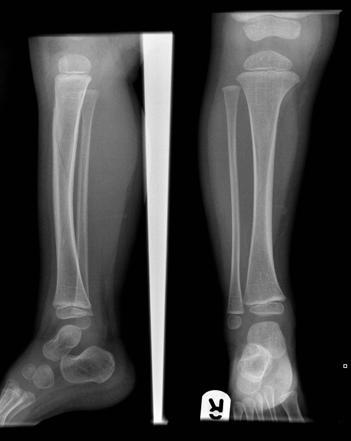

What is going on in this radiograph?

This is a Toddler’s fracture

The mechanism/traumatic event is often not witnessed. Radiographs may reveal a non-displaced spiral fracture of the tibia without fibular involvement.

However, initial radiographs may be negative and only after there has been time for periosteal reaction (~1 week, maybe more) will you be able to see the fracture.